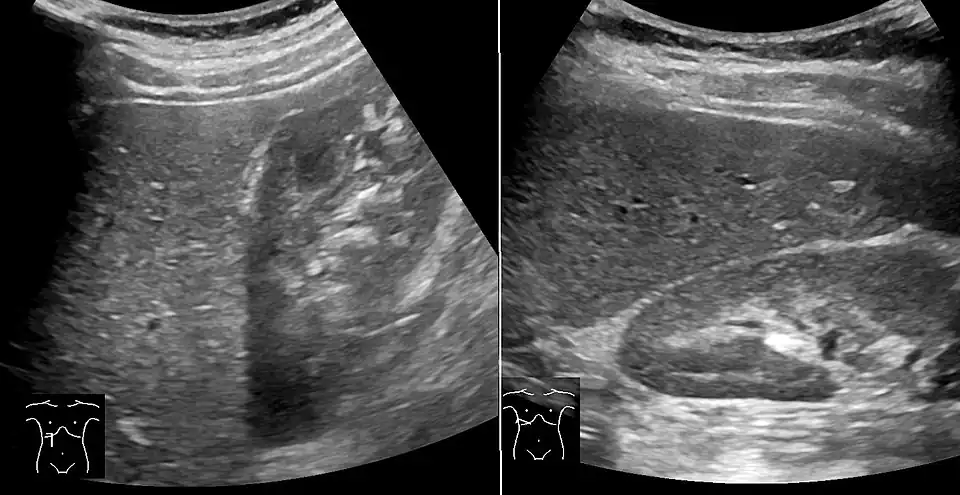

On X-ray computed tomography (CT), the increased fat component will decrease the density of the liver tissue, making the image less bright. Typically the density of the spleen and liver are roughly equivalent. In steatosis, there is a difference between the density and brightness of the two organs, with the liver appearing darker.[12] On ultrasound, fat is more echogenic (capable of reflecting sound waves). The combination of liver steatosis being dark on CT and bright on ultrasound is sometimes known as the flip flop sign.

On abdominal ultrasonography, steatosis is seen as a hyperechoic liver as compared to the normal kidney.

Abdominal ultrasonography with the liver and kidney side by side (left image) may give a false impression of hyperechogenic liver, so it's preferably done with the organ borders facing the ultrasound probe (right image, of the same case). -